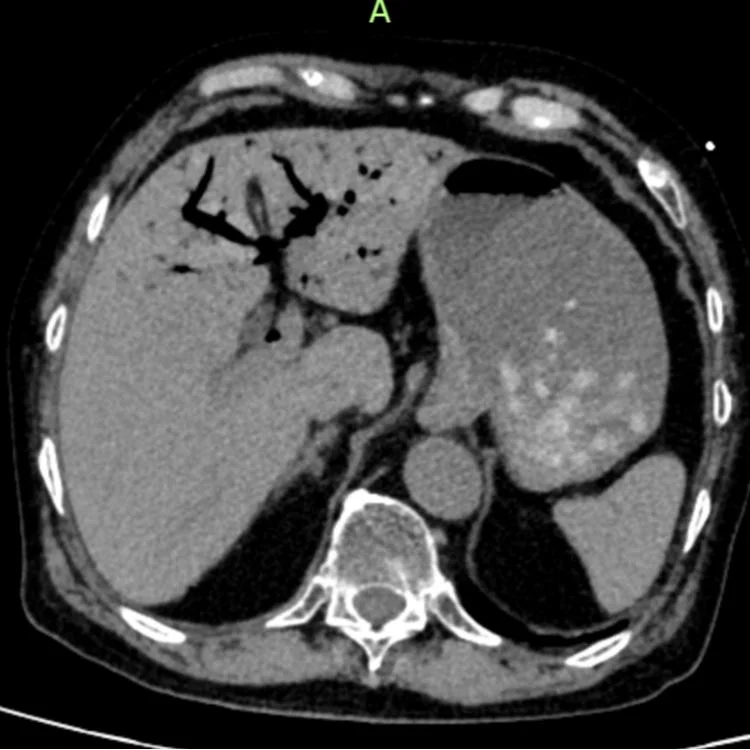

肝门静脉积气

医学上的“死神之征”

急诊CT结果让医护人员高度警惕:肝门静脉及肠系膜静脉广泛积气。